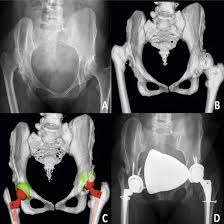

NCCT Both Hip Joint scan uses X-rays to make cross-sectional pictures of both your hip joints at the same time. Unlike traditional X-rays, this scan shows bones, soft tissues, and joints in detailed layers. The word ‘Non-Contrast’ means no dye injection is needed. The machine takes hundreds of pictures and combines them to show every part of your hip joint clearly. This helps doctors see problems like small breaks, wear and tear, fluid collection, or early arthritis signs. The scan checks both hips together, making it easier to compare and find differences between your right and left hip.